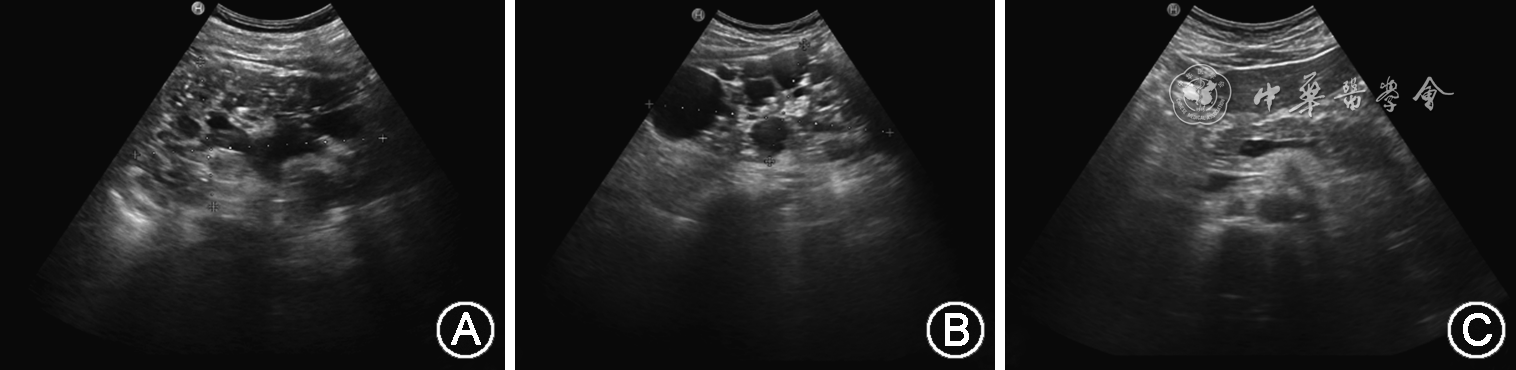

1. 先证者临床表型:先证者入院血压:170/103 mmHg(1 mmHg=0.133 kPa);24 h动态血压结果提示:(1)24 h血压平均值:139/86 mmHg;(2)白天血压均值:141/85 mmHg;(3)夜间血压平均值:135/87 mmHg;(4)夜间血压下降率:2.4%~4.3%,24 h血压呈非勺型。尿常规检测潜血阳性,血肌酐升高。B超示:双肾体积增大并异常回声,考虑成人型多囊肾并多发结石;肝囊肿。主要表现为:双肾体积增大,大小分别约130 mm×76 mm(左)、144 mm×72 mm(右);肾内充满众多大小不一的无回声区,较大分别约33 mm×22 mm(左)、48 mm×44 mm(右),囊与囊之间见少量肾实质回声;集合系统受压变形,肾盂、肾盏内见多个点状、斑状或团状强回声,左肾集合系统分离约17 mm,见图2A、B。肝脏实质回声欠均匀,肝内见数个无回声区,较大约15 mm×11 mm,边界清,内透声好,见图2C。中腹部CT示:双侧多囊肾改变伴左肾结石,肝脏多发囊肿。